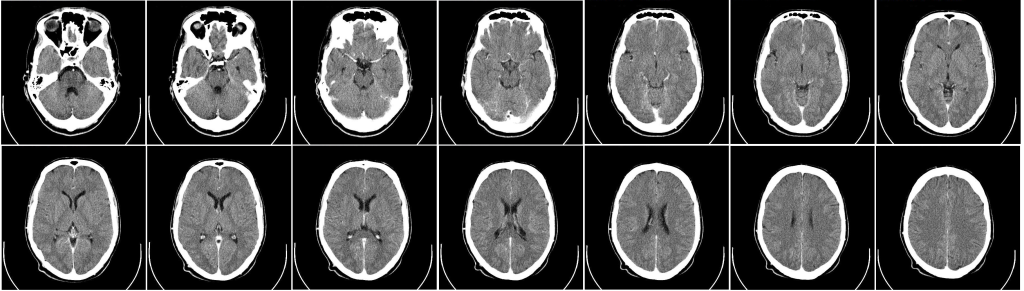

- Компьютерная томография (КТ) и магнитно-резонансная томография (МРТ) — визуализируют структуры мозга и выявляют возможные патологии сосудов, опухоли, воспаления.